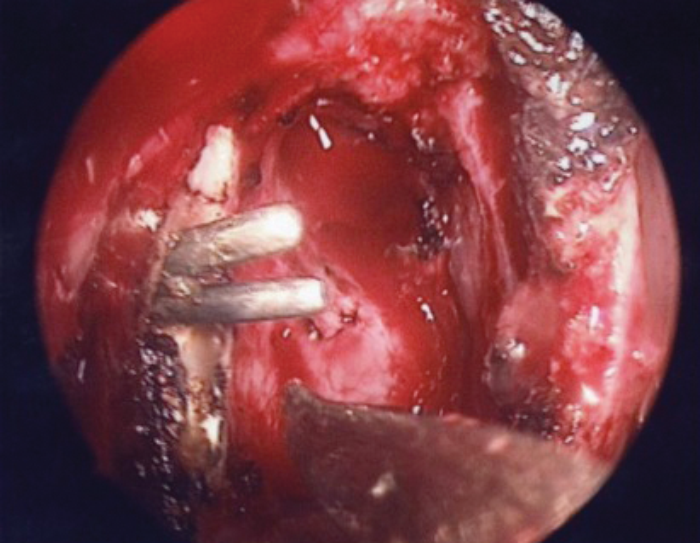

A wide nasolacrimal window is created. Silastic lacrimal stents are then placed via both upper and lower canaliculi, retrieved endonasally (Figures 7a & b) and tightened over a 18 gauge venflon sheath / silastic tubing (Figure 8) to prevent upward migration of the stent knot. The stent loop is ensured not to be too tight as it may cheese wire through the puncta. We prefer using ligaclips to stabilise the stents (Figures 9a & b) in place of knots to avoid any risk of slippage of the knot leading to stent laxity. The nasal mucosa is trimmed and folded back to cover the exposed bone and haemostasis achieved with suction diathermy.

Figure 7b. Silastic stenting of both upper and lower canaliculi and

retrieval of the tips through the dacryocystostomy.